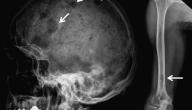

يُصنف مرض الميلانوما على أنه نوع من أنواع سرطان الجلد الذي ينشأ من خلايا الميلانينية التي تقوم بإنتاج وإفراز صبغة الميلانين حيث تحدث طفرة لهذه الخلايا تجعلها تنقسم بطريقة غير منظمة، وبالرغم من أنّه ليس الأكثر شيوعًا إلا أنه الأكثر شراسةً منها حيث يميل إلى الإنتشار سريعًا إلى جميع أجزاء الجسم مما يجعل من الصعب علاجه، لذلك من الضروري جدًا تشخيصه مُبكرًا، وتوفير العلاج المناسب بسرعة، ومن عوامل خطر حدوث هذا السرطان التعرض الكثير لأشعة الشمس، وعمل جلسات تسمير البشرة، ووجود تاريخ عائلي للإصابة بهذا المرض؛ لذلك يجب ع الأشخاص الأكثر عرضًا لهذا المرض مراقبة أي تغييرات تحدث للشامات في الجلد، واستخدام واقي شمس للحد من التعرض للشمس، وفي هذا المقال سيتم الإجابة عن سؤال هل مرض المايلوما خطير.[١]

بالإجابة عن سؤال هل مرض المايلوما خطير فإن هذا المرض يعد من سرطانات الجلد التي تنتشر بسرعة في الجسم، وتبدأ عادة على شكل شامة سوداء في الجلد، وقد تظهر في أنسجة أخرى مثل العينين، والأمعاء، ومن المهم مراقبة أي تغييرات تحدث للشامات التي في الجلد حيث تم تسجيل ٩ آلاف حالة وفاة بسبب المايلوما في الولايات المتحدة الأمريكية عام ٢٠١٣، وتختلف نسبة النجاة من هذا المرض بناءً على المرحلة المُصنف فيها، حيث ينقسم هذا المرض إلى أربعة مراحل، بالإضافة إلى التطورات الجديدة في علاج السرطانات، وإستجابة الشخص للعلاج، وسنّ المريض حيث تكون نسبة نجاة المرضى كبار السنّ أقل من المرضى الصغار.[٢]

ويعد المايلوما من أكثر سرطانات الجلد خطورةً وشراسةً، ويظهر على شكل بقعة جديدة في الجلد أو على شكل تغير في الشامات الموجودة سابقًا، ويعتمد علاجه على مدى إنتشاره إلى أجزاء الجسم الأخرى، وفي حال عدم علاجه فإنه سينتشر، ويصبح غير قابل للشفاء نهائيًا، ويمكن وقتها علاج الأعراض فقط للتخفيف عن المريض، ويعد التعرض الزائد لأشعة الشمس، أو التعرض لها من مصادر صناعية من أكثر العوامل خطورةً لحدوث هذا المرض؛ لأن ذلك يدمر الجلد بشكل دائم مع كل تعرض لأشعة الشمس مما يجعل خلايا الجلد تنقسم بشكل غير طبيعي، ونسبة التعافي من هذا المرض تتحسن مع مرور السنين وتكون نسبة نجاة الأناث خلال أول خمس سنين من التشخيص بالمرض ٩٤٪ وذلك أكثر من الذكور التي تكون نسبة نجاتهم ٨٩٪، وذلك يُمثل إجابة عن سؤال هل مرض المايلوما خطير.[٣]